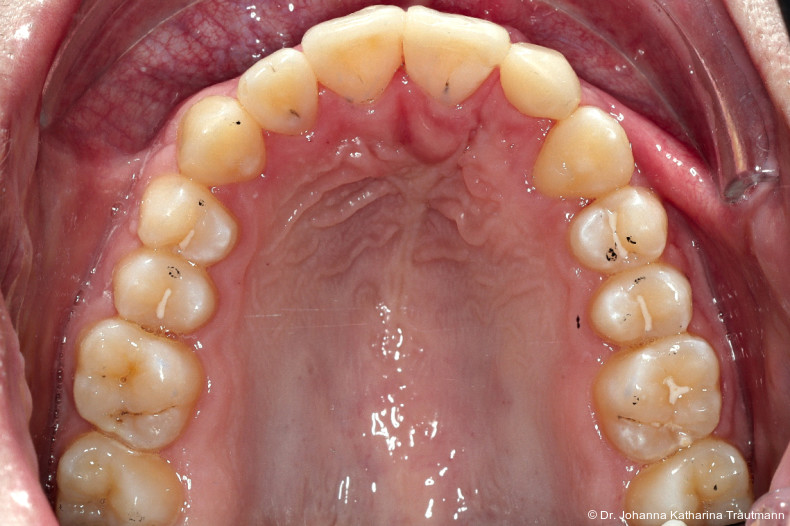

Das Fernröntgenseitenbild zeigte eine skelettale Klasse IIAnomalie mit einem Wits von 5,6 mm, bei einer tiefen Konfiguration (ML NL = 16,5°) mit bialveolär retrudierten Fronten (OK1NA = 5,9°; UK1NB = 10,4°), was sich auch in der Modellanalyse widerspiegelte. Hier zeigte sich zudem ein schmaler Oberkiefer mit multiplen Kippungen und Rotationen in der Front, einem hypoplastischem 22 sowie einer Mesialwanderung des 16. Des Weiteren zeigte sich eine asymmetrische Bisslage mit 1 PB distal rechts und ½ PB distal links bei einem Overjet von 2,5 mm sowie einem Overbite von 5 mm. Während im Unterkiefer bereits die zweite Zahnwechsel phase begonnen hatte, zeigte sich im Oberkiefer noch kein Wechsel in den Stützzonen. Gerade bei Patienten mit Spaltbildungen ist eine engmaschige Überwachung des Durchbruchs der oberen Eckzähne essenziell. Während bei der Allgemeinbevölkerung die Prävalenz von verlagerten Eckzähnen bei ca. 2,8 Prozent liegt2, ist diese bei Patienten mit Lippen-Kiefer-Gaumen-Spalten um den Faktor 10 erhöht.3, 4 Als klassische Risikofaktoren gelten zudem Platzmangel, transversale Enge aber auch Fehlstellungen, Nichtanlagen oder Hypoplasien der zweiten Schneidezähne. Diese übernehmen normalerweise die Funktion der Leitschiene für den S-förmigen Durchbruch der Eckzähne. Im vorliegenden Patientenfall kommen also mehrere Risikofaktoren für eine Verlagerung zusammen, was die rechtzeitige Diagnostik zur Abklärung einer Durchbruchsproblematik rechtfertigt. Da im Spaltbereich auch zusätzlich ein ausgeprägtes Knochendefizit vorliegen könnte, sollte auch immer die Option einer sekundären Osteoplastik abgewogen werden, deren Indikation und Timing optimal zum Durchbruch der Canini angepasst werden sollte.5

Nach transversaler Nachentwicklung der Maxilla mittels GNE nach Veltri wurde der Zahn 23 geschlossen freigelegt und an einem individualisier ten TPA nach distal angebunden. Zur Aufrichtung der Front und Mesialisierung des hypoplastischen Zahnes 22 kam zusätzlich eine 2x3Mechanik zum Einsatz. Eine rein translatorische Bewegung eines Zahnes ist auch mit einer festsitzenden Apparatur schwer zu erreichen, da der Kraftansatzpunkt nicht identisch mit dem Widerstandszentrum des Zahnes ist.7 Diese Problematik kann einerseits durch das Einbringen eines Versetzungsmomentes adressiert werden, andererseits durch eine Verlagerung des Kraftansatzpunktes. Angelehnt an den von Hong et al. beschriebenen Power Arm 8 wurde hierfür palatinal an Zahn 22 ein cranial gerichteter Hook angebracht (Abb. 3). Da Zahn 22 aufgrund seiner Hypoplasie eine verkürzte Wurzel aufwies, konnte so die Distanz zwischen Widerstandszentrum und Kraftangriffspunkt effizient reduziert werden. Eine weitere biomechanische Schwierigkeit stellte das geringe Alveolarknochenangebot im Spalt bereich mesial von 22 dar. In Bereichen mit Knochendefizit verschiebt sich das Widerstandszentrum nach apikal und wie in diesem Fall zusätzlich nach distal.9, 10 Um dem erhöhten Risiko für Kipp bewegungen entgegenzuwirken, muss hier besonders auf die Steuerung des M/F-Quotienten geachtet werden. Der vestibulär durchgebrochene Zahn 13 benötigte keine Freilegung. Um seine korrekte Einstellung zu ermöglichen, wurde die Mesialwanderung des Zahnes 16 mithilfe des TPAs korrigiert sowie eine Mittellinienkorrektur nach links mittels 2x3 Mechanik durchgeführt.